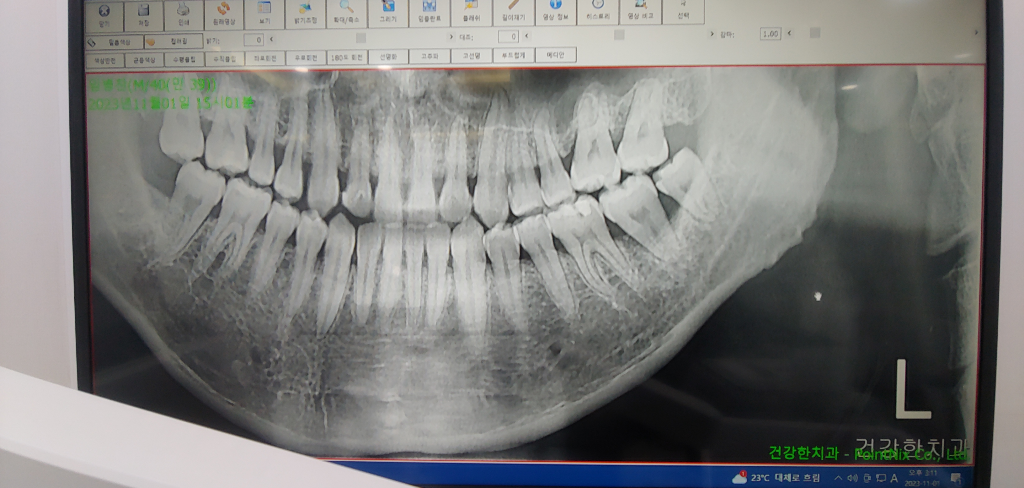

파노라마 사진 한장으로 치료 계획을짤 수는 없습니다. 치실은 하셔도 되지만 다른치과도 가서 진단 받아보시는게 좋겠습니다.

x ray 사진상에서 어금니 잇몸뼈가 내려간 상태입니다. 일단 사랑니 먼저 뽑아 보시고 추후 어금니가 씹을 때 불편하면 어금니 빼고 임플란트 해야 하며, 음식물 씹을 때 어금니 불편감이 없다면 어금니 빼지 않고 계속 사용해도 됩니다.

두번째 큰 어금니의 경우 치아 자체보다는 잇몸이 문제인 것이 맞습니다. 정확히 말하면 잇몸질환(잇몸 속 염증)으로 인해 잇몸뼈가 녹아내린 상태입니다. 그렇기 때문에 치아도 동요도가 있는 것이고요. 다만, 잇몸치료를 하면서 발치시기를 조금 늦출 수는 있습니다. 지금 당장 뽑기에는 사실 아주 심각한 상태로 치아가 흔들리지는 않을 것 같고 별다른 잇몸,치아 통증이 없다면 잇몸치료를 먼저 권해드립니다.

추가적으로 혹시 왼손잡이라면 왼손으로만 이를 닦으면 왼쪽이 구석구석 닦이지 않을 확률이 높습니다. 양치 시 양손을 다 사용해주시는게 좋습니다. 유독 오른쪽에 비해 왼쪽 위,아래가 상대적으로 상태가 더 안 좋아보여서 말씀드렸습니다

왼쪽아래 사랑니 앞의 치아는 사진으로는 크게 문제가 있어 보이지는 않습니다.